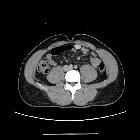

solitärer fibröser Tumor des Retroperitoneums

CT reveals a well-circumscribed, smooth, and lobulated soft tissue mass that may contain scattered calcifications. Smaller tumors tend to enhance homogeneously, whereas larger lesions may have central tubular or rounded low-attenuation areas due to cystic or necrotic change.